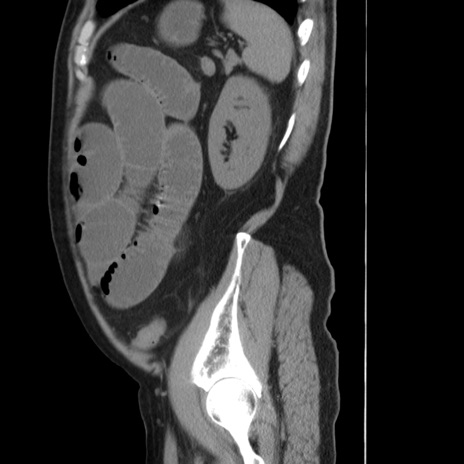

症例20(矢状断像)

【症例】 60歳代男性

【主訴】 腹部膨満、嘔吐

【現病歴】5日前頃より倦怠感を認め食事量減少し4日前の朝嘔吐、食事摂取困難となった。 3日前近医受診し点滴施行され整腸剤などを処方された。 当日他院を受診し、腹部膨満著明、炎症反応の上昇(CRP10.8、WBC11200)あり、紹介受診となる。

【身体所見】 意識JCS1 受け答えがはっきりしないBP 111/57mHg、 P 67bpm、、BT35.2°C、SpO2 97%(RA)、 腹部:膨隆、打診で鼓音あり、全体的に圧痛有り、腸蠕動音(-)、反跳痛ははっきりせず。

【データ】WBC 11400、CRP 14.20